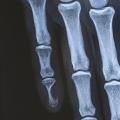

Des érosions osseuses peuvent être visibles sur les radiographies simples : un festonnage ou une empreinte de la phalange distale est mis en évidence chez 36 % des patients,15 jusqu’à de volumineuses lacunes osseuses (fig. 2).